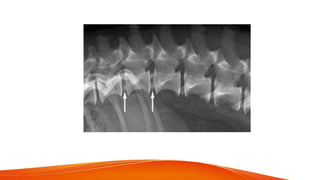

• Radiographic signs : narrowing of disc space , sclerosis ,

spondylosis, vertebral lysis

• Spinal pain, neurologic deficit , paresis / paraplegia - nerve root & spinal cord compression • Radiographic signs : narrowing of disc space , sclerosis , spondylosis, vertebral lysis